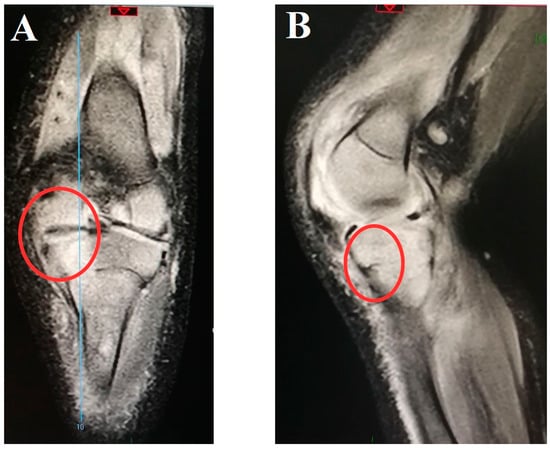

| Magnetic resonance imaging performed a (n, %) | 32 (80) | 28 (93.3) | 4 (40) | 0.001 * |

| Magnetic resonance imaging positivity b (n, %) | 31 (96.8) | 28 (100) | 3 (75) | <0.001 * |

Magnetic resonance imaging alterations c (n, %)

| 17 (54.8) 9 (29.0) 5 (16.1) 6 (19.3) 2 (6.4) 1 (3.2) 1 (3.2) 1 (3.2) | 16 (57.1) 9 (32.1) 5 (17.8) 6 (21.4) 2 (7.1) 1 (3.5) 1 (3.5) 1 (3.5) | 1 (33.3) - 0 0 0 0 0 0 | 0.02 * - 0.31 0.31 1 1 1 1 |